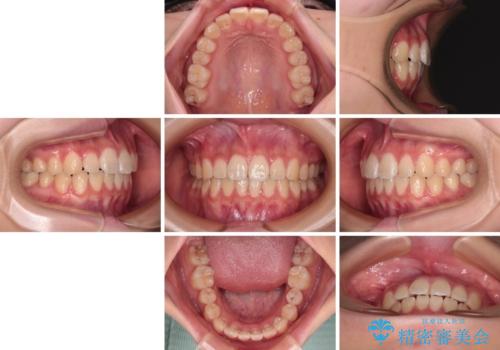

- クリアブラケット

- 11ヶ月

- 10-30回